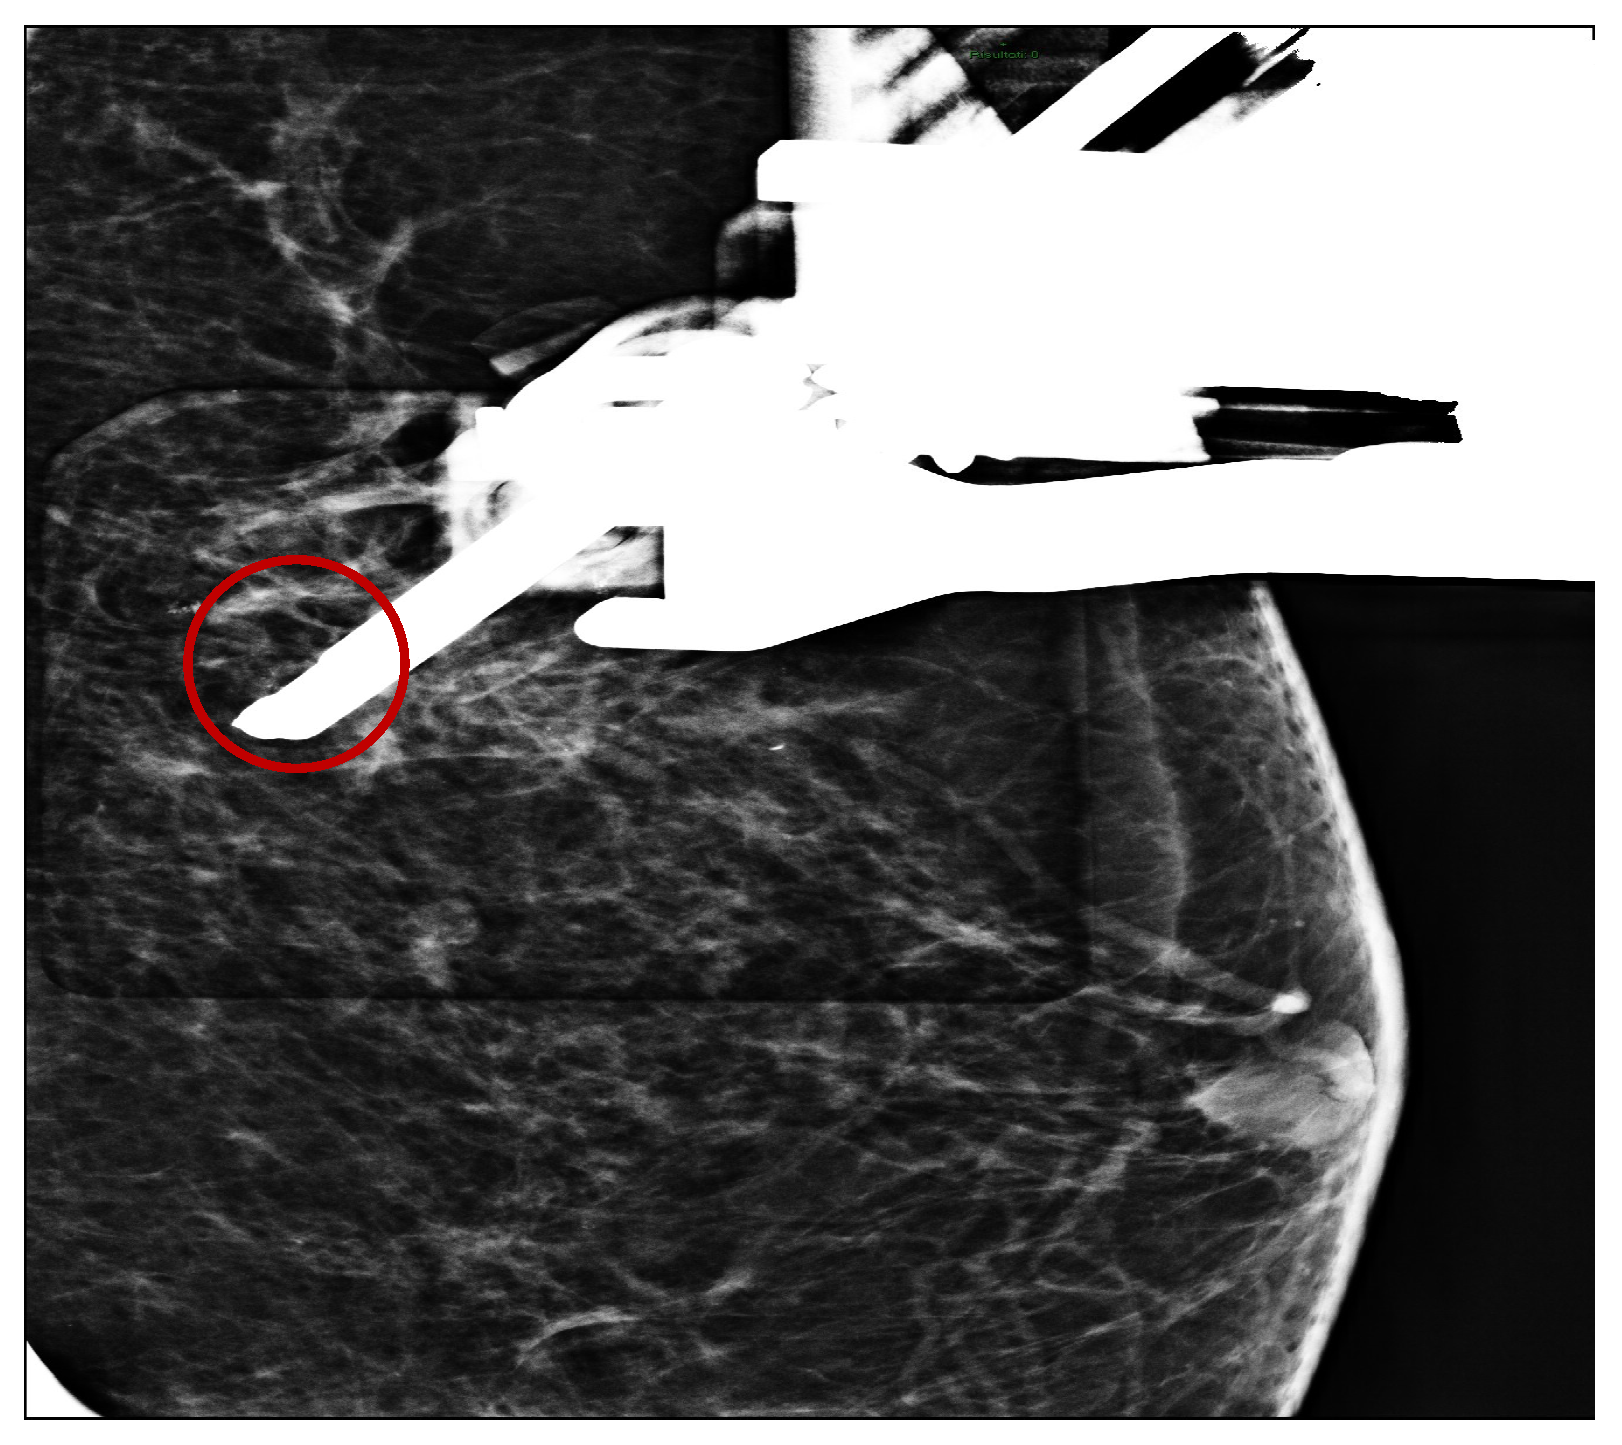

Vascular Complications following Vacuum-Assisted Breast Biopsy (VABB): A Case Report and Review of the Literature

2. Case Report